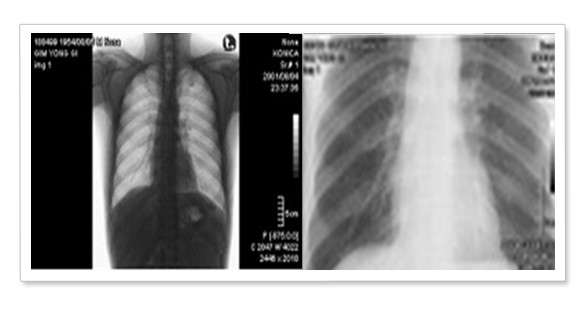

Read More진수의 척추 검진 2014년 8월 초, 여름방학 동안 본격적인 치료를 받기 위해 진수는 서울대학교 병원에서 척추측만증에 대한 진료를 받았습니다. 태아때 척추생성 과정에 이상이...